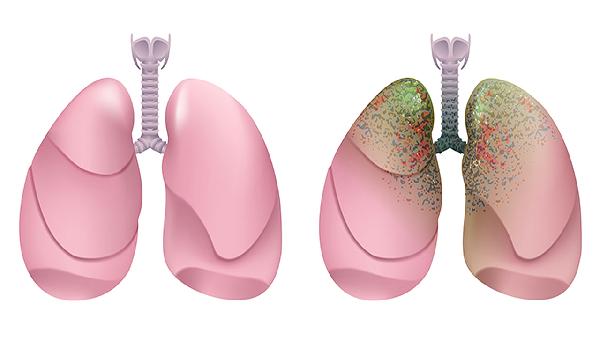

右肺下叶基底段实性结节通常指影像学检查发现的肺部局部密度增高病灶,可能由炎症、结核或肿瘤等疾病引起。